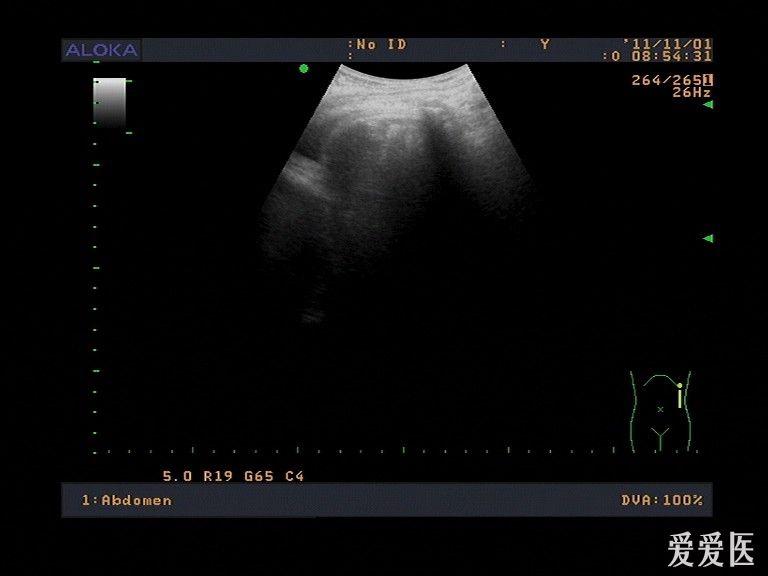

胸水的超声测量示意图

胸水的超声测量示意图,胸水的超声测量图解

胸水的超声测量图解

超声测胸腔积液图解